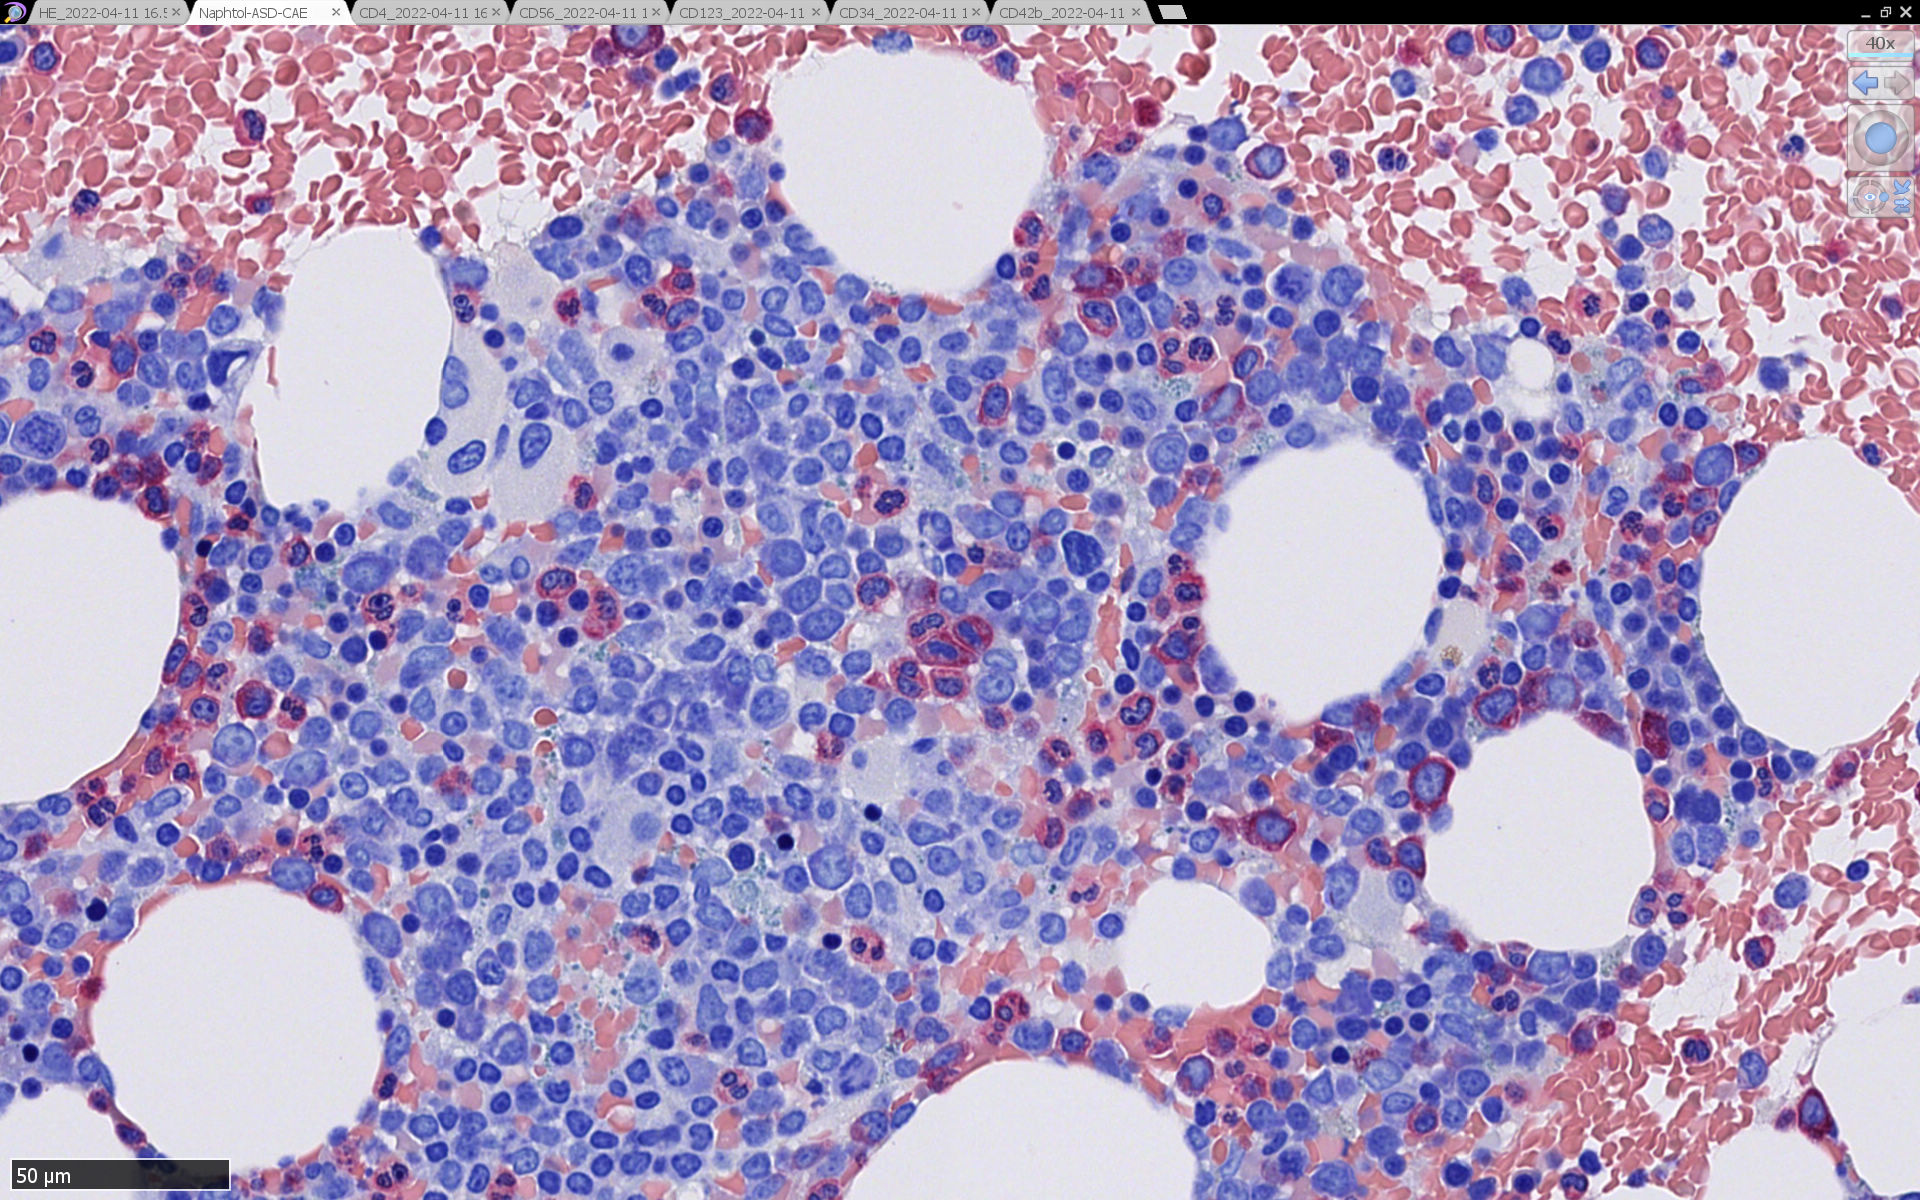

症例骨髄に認められた異形成造血所見

Mgkは低分葉, 円形単核の細胞が多く, 分離円形核のMgkもみられた. 赤芽球はproerythroblstsのみの小集簇や孤在性出現あり. 成熟赤芽球が乏しい. 顆粒球系細胞も分葉好中球への分化像が少ない.

免疫染色では, HbFを発現する赤芽球の集簇巣が散見しているほか, p53陽性細胞が軽度に増加している. CD34陽性細胞増加はなし.CD42b染色でmicroMgkはみられなかった. 異形成造血が強く疑われる.